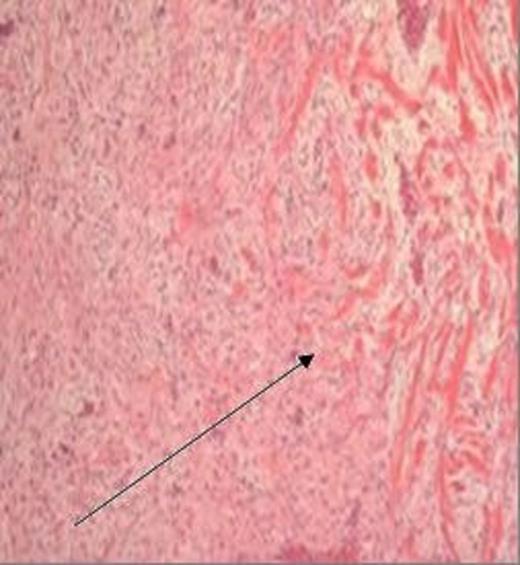

On histological assessment the specimen showed bland spindled cells arranged in intersecting fascicles. Involvement included the small bowel mesentery and jejunal muscularis propria with focal extension into submucosa (figure 4). The microscopic margin of the tumour was ill defined but appeared clear of the resection limit. Immunohistochemistry showed strong nuclear expression for beta-catenin but was negative for C-KIT, CD34 and DOG1 consistent with a diagnosis of desmoid tumour (3,4,5).

H&E stained section, magnification x 40, demonstrating a bland spindled cell lesion arranged in intersecting ill-defined fascicles, with some intervening collagen fibres and relatively limited infiltration at the lesion margin (arrow)